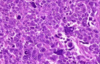

Wilms tumor Microscopic features (3)

- Triphasic pattern*

- Primitive blastema (small/dark undifferentiated cells)

- Epithelial component (abortive tubules/glomeruli)

- Stroma (Fibrous or myxoid patterns; may contain mesenchymal elements (cartilage, muscle, bone)

Wilms tumor microscopic features (3):

Triphasic pattern

- Primitive blastema (small/dark undifferentiated cells)

- Epithelial component (abortive tubules/glomeruli)

- Stroma (Fibrous or myxoid patterns; may contain mesenchymal elements (cartilage, muscle, bone)

Wilms Tumor

What is the significance of this in WIlms Tumor?

ANAPLASIA

Determines the Prognosis of Wilms tumor

- Pleomorphism, hyperchromatism, abnormal mitoses –> more aggresssive; higher resistance to chemotherapy

- Stage matters also w/ Prognosis*